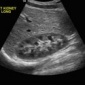

Ultrasound imaging uses a transducer or probe to generate sound waves and produce pictures of the body's internal structures. |